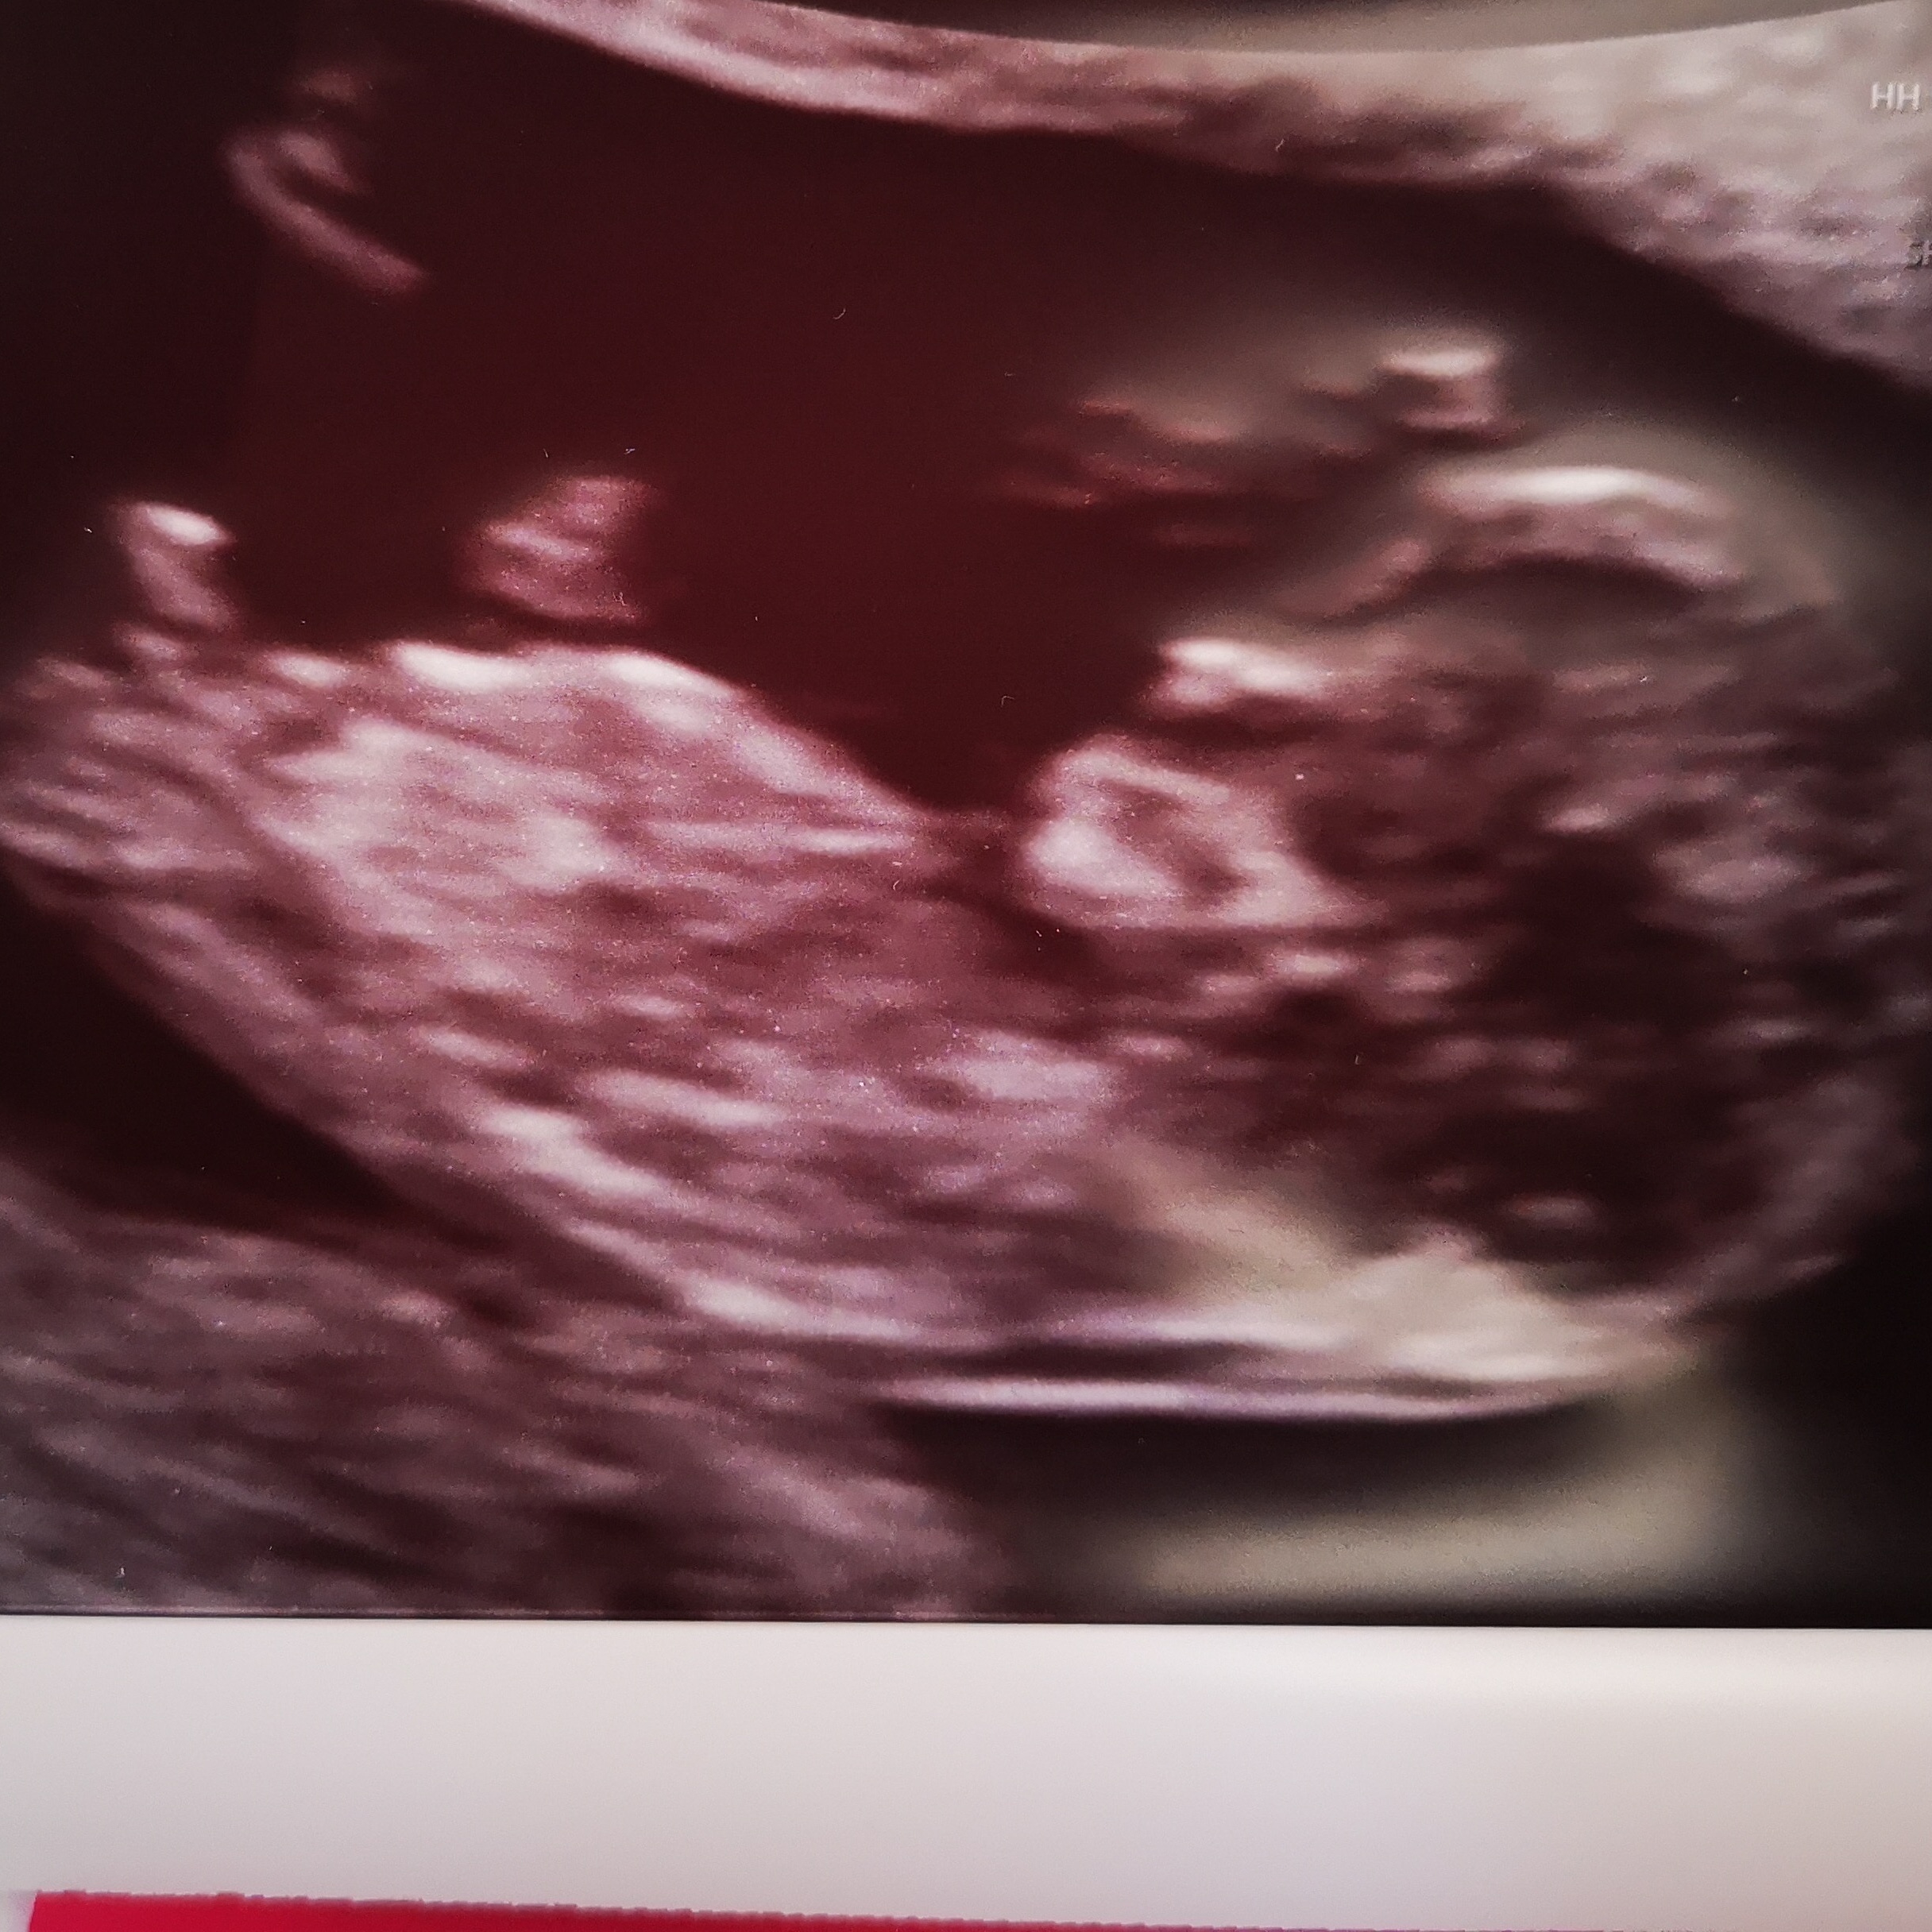

Attachment 40081

Hi thanks for your reply ladies .

I have quite alot of ss from the video that was taken during the scan. The nub is pointing up throughout, this is the best ss I could get xx

The nub does look very boyish for that age but it's still very early. Closer to 13 weeks is better for nub guessing.